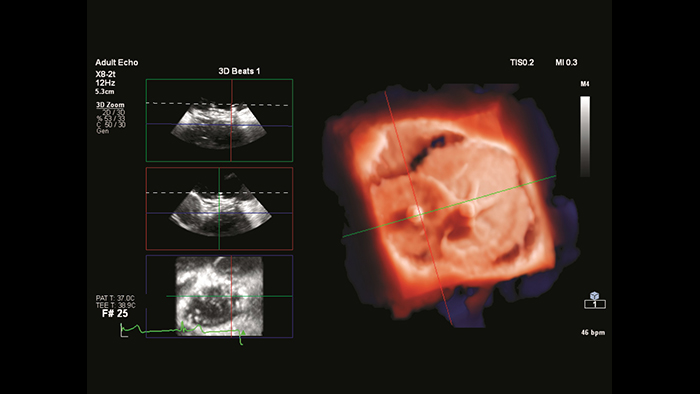

Segmentación del modelo cardiaco de EchoNavigator

Cierre de la comunicación interauricular con fusión en tiempo real de EchoNavigator